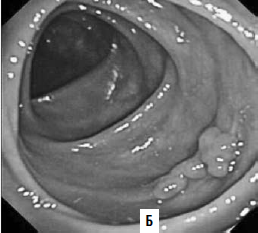

Виртуальная колоноскопия. В последние годы для диагностики опухолей ободочной кишки применяют т. н. виртуальную колоноскопию. Метод представляет собой компьютерное томографическое исследование ободочной кишки после предварительного ее заполнения воздухом. Отличие получаемых результатов от классической КТ в том, что программное обеспечение на основании получаемых с датчиков данных строит трехмерную модель кишки, очень похожую на картину, видимую в обычный фиброколоноскоп (рис. 186). Данное исследование значительно легче переносится больными в сравнении с оптической фиброколоноскопией. Но диагностические возможности метода меньше, чем ФКС: полипы размером менее 1 см не видны.

Рис. 186. А – виртуальная колоноскопия, Б – фиброколоноскопия